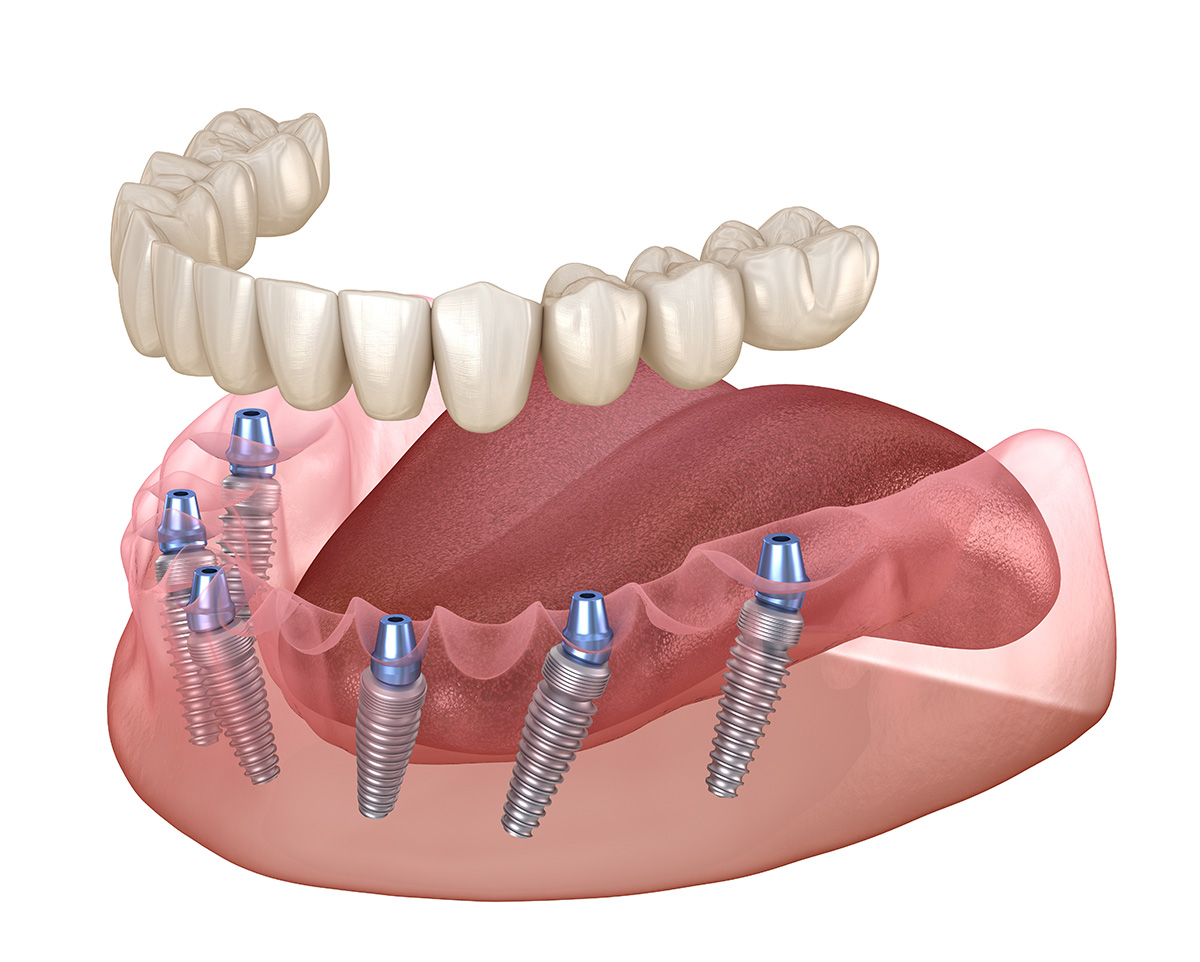

Les systèmes All-on-4 et All-on-6 offrent une solution avancée pour les patients édentés souhaitant retrouver un sourire fonctionnel et esthétique. Ces techniques innovantes consistent à placer quatre à six implants dentaires stratégiquement dans la mâchoire afin de supporter une prothèse dentaire fixe.

Contrairement aux solutions traditionnelles, ces systèmes permettent une réhabilitation complète en une seule intervention, avec une prothèse provisoire posée immédiatement après l’opération.

Pour garantir un positionnement optimal des implants et une stabilité à long terme, la chirurgie guidée joue un rôle essentiel. Cette technique repose sur un plan de traitement numérique détaillé, élaboré à partir d’un scanner 3D et d’une modélisation informatique.

Une fois le positionnement des implants déterminé avec précision, un guide chirurgical est imprimé en 3D pour assurer une insertion idéale des implants. Cela permet de réduire les risques, d’améliorer le confort post-opératoire et d’optimiser la durée de cicatrisation.